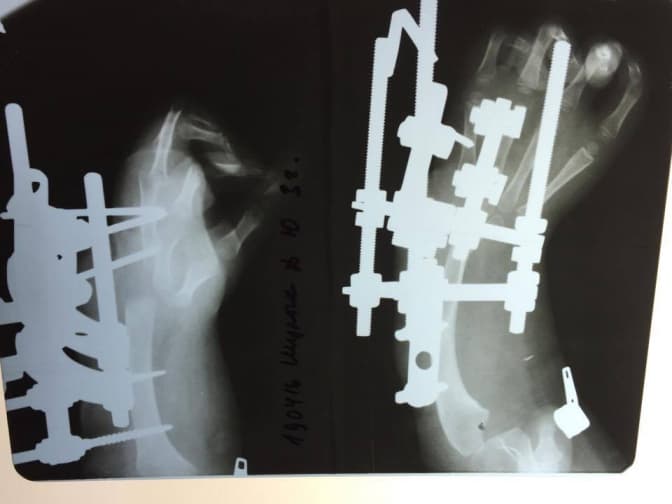

Як розповіла Tvoemisto.tv координатор проекту надання високоспеціалізованої ортопедичної допомоги в «ОХМАТДИТі», завідувачка ортопедичного відділення Злата Кузьо, раніше цій дитині провели два етапи хірургічних втручань: перший – у квітні 2016-го року – виведення кисті з променевої девіації в центральне положення за допомогою апарату зовнішньої фіксації; другий – у червні 2016-го року – центрація кисті на ліву ліктеву кістку.

Рентгенограма 1-го етапу